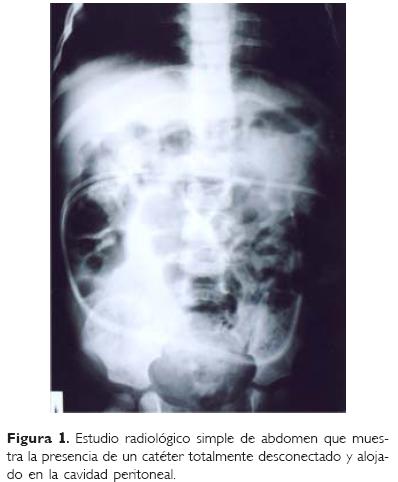

Femenino de cuatro años de edad que procede de la Ciudad de México, y en la que se refiere el antecedente de infección del sistema nervioso central por Haemophylus influenzae al año de edad, lo que le ocasionó como complicación la formación de un higroma subdural frontoparietal bilateral. Ocho días después de identificado el problema se le efectuó una derivación subaracnoideoperitoneal con un catéter de silastic (Medtronic, Minneapolis, Minnesota USA). La evolución fue aparentemente desfavorable ya que reingresó 10 días después por convulsiones tónicoclónicas generalizadas. Dentro de la unidad se le efectuó estudio radiológico simple de abdomen, encontrándose como hallazgo la migración casi completa del catéter hacia la cavidad peritoneal, por lo que éste se rescató a través de una incisión en piel y se recolocó una semana después en el otro lado. A los seis meses de ser egresada, nuevamente fue hospitalizada en su unidad de origen por cuadro similar al anterior. Se le realizó un estudio radiológico de control (Fig. 1) en donde se observó migración completa del catéter, motivo por el cual es enviada para su extracción al Departamento de Cirugía de nuestra unidad a la que acude con el catéter en una bolsa de plástico y totalmente asintomática. En esa ocasión se le practicó radiografía de abdomen y encima de ésta se colocó el catéter que recién había expulsado (Fig. 2).